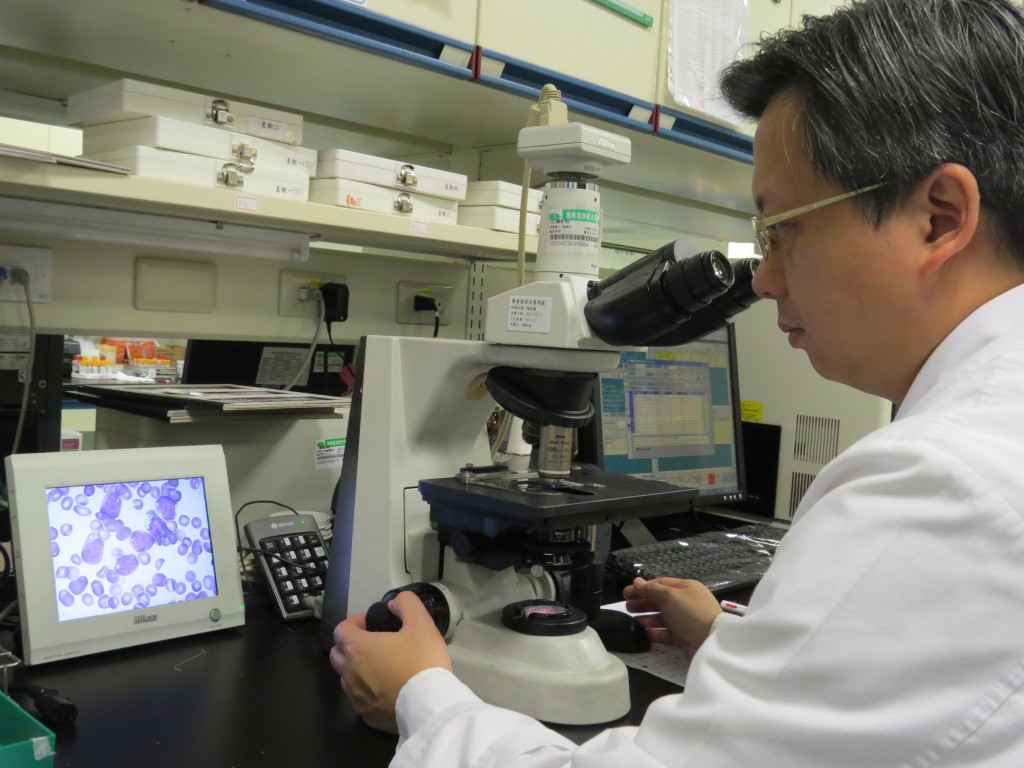

對此,台中慈濟醫院血液腫瘤科主任李典錕醫師表示,該名男子之所以罹患血癌,主要是因為「基因突變造成」,不過血癌並非完全無藥可治,且治癒成功率高達七成,於是開始為李姓男子進行化療。